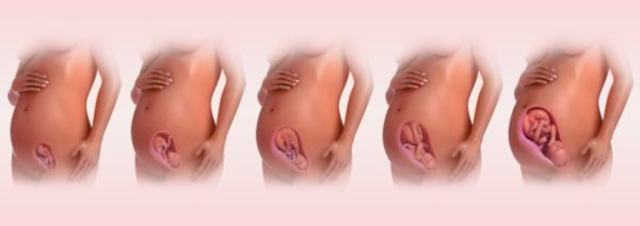

El cigoto se convierte en embrión. desarrolla el sistema circulatorio, el corazón y brotes de lo que posteriormente serán los brazos y piernas. presenta una cola que es el inicio del cordón umbilical. Se forman los dedos de las manos y pies, los labios, el hígado, orejas y ojos.

Las uñas empiezan a crecer y los huesos a endurecer, los riñones producen orina y los órganos sexuales empiezan a desarrollarse.

Comienza a crecer el cabello y los órganos sexuales interno se ubican en la posición de la cadera

Crece un bello fino en el cuerpo y una capa de grasa que ayudará a proteger la piel del bebé cuando nazca.

Aparecen pestañas y cejas.

Inicia cambios físicos, regula actividades y momentos de sueño, los parpados se abren y se forma la retina.

El vello o lanugo se cae, y en el sexo masculino los testículos inician el descenso al escroto.

El feto tiene mas grasa corporal, las pupilas se contraen al exponerse a la luz.